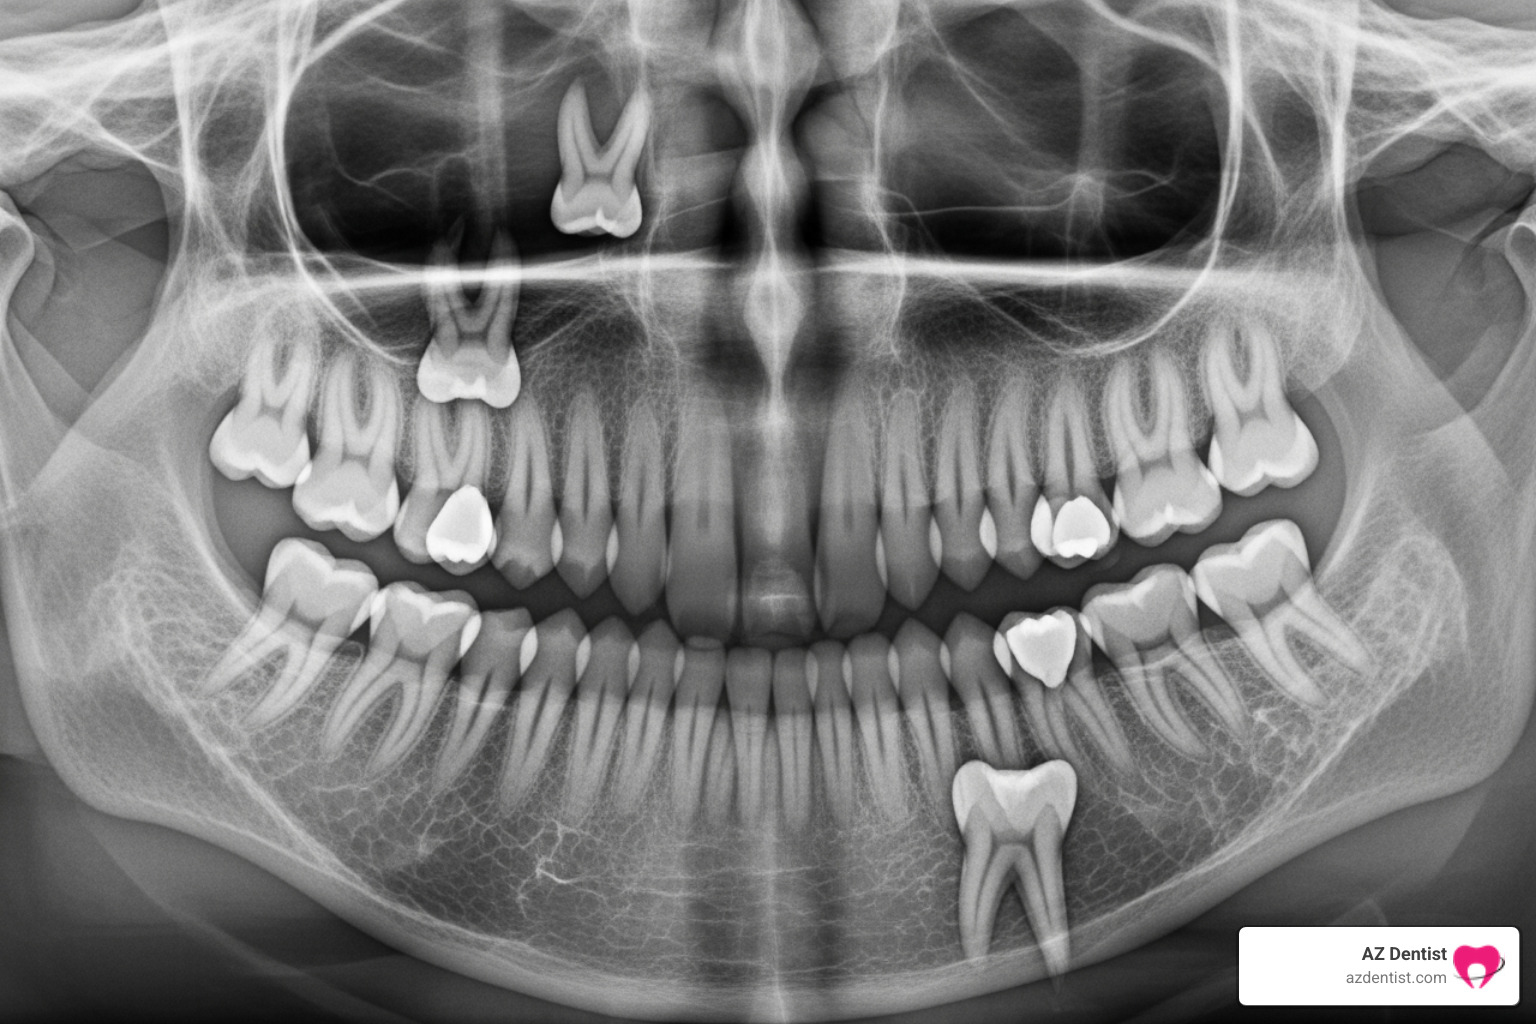

- X-rays and 3D Imaging: To get a clear picture of your wisdom teeth, their position, and their relationship to surrounding structures like nerves and sinuses, we’ll take advanced images. This often includes panoramic X-rays and a Cone Beam Computed Tomography (CBCT) 3D scan. This detailed imaging allows us to plan your surgery with precision and minimize risks.